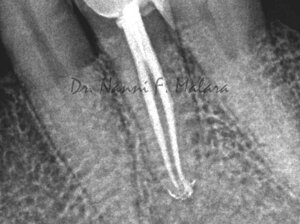

Premolare affetto da lesione periapicale (Alla radiografia si presenta come area scura intorno alla radice)

Terapia endodontica con sigillo tridimensionale del sistema canalare

Il controllo radiografico eseguito ad 8 mesi evidenzia l'avvenuta guarigione con il riassorbimento completo della lesione apicale.